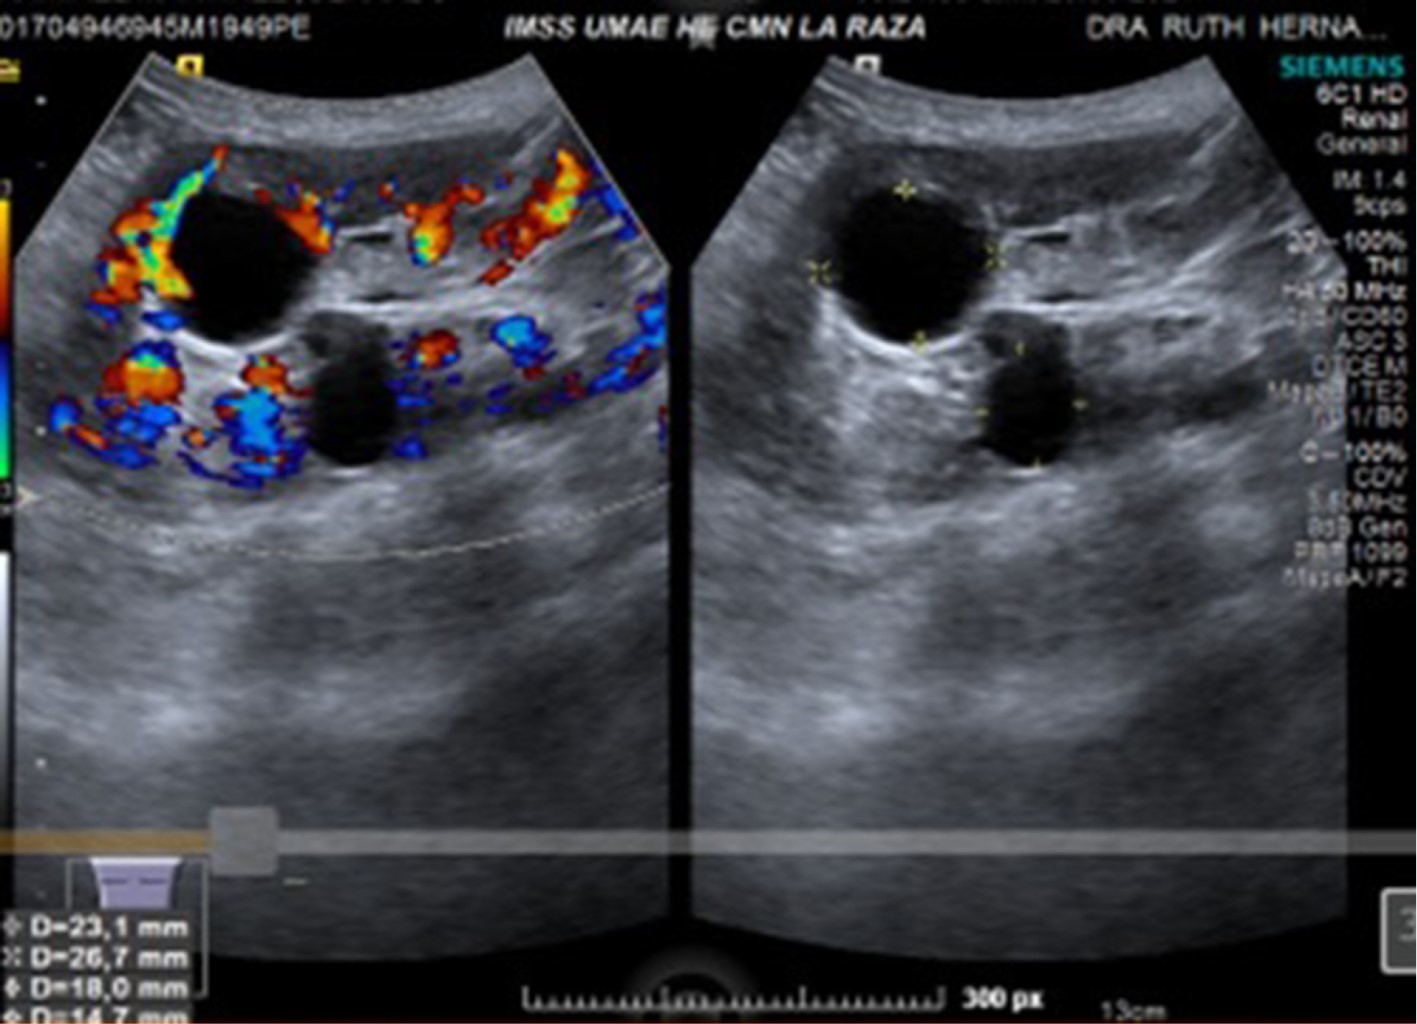

Figure 1